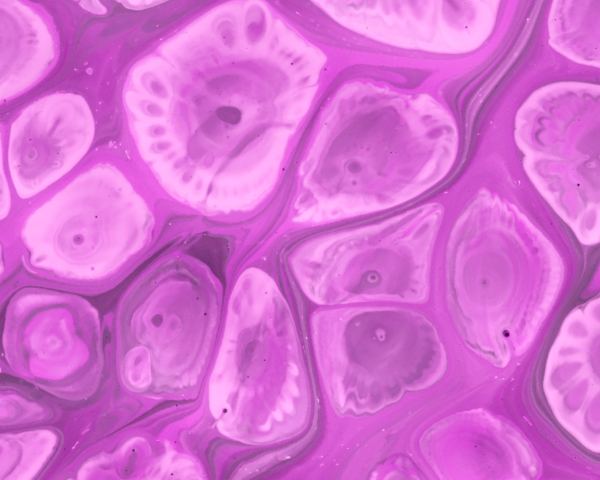

여성과 남성의 생식능력은 나이가 들수록 수적으로나 질적으로 감소합니다.

가임력 보존은 암 치료, 생식기 수술 등으로 인해 생식 기능이 저하될 가능성이 있는 경우, 생식세포(난자, 정자, 배아)를 동결 보존하여 미래의 임신 가능성을 유지하는 치료입니다.

또한, 고령임신이나 노산이 예상되는 경우에도 건강한 생식세포를 보존해 두면 나중에 높은 임신 성공률을 기대할 수 있습니다.